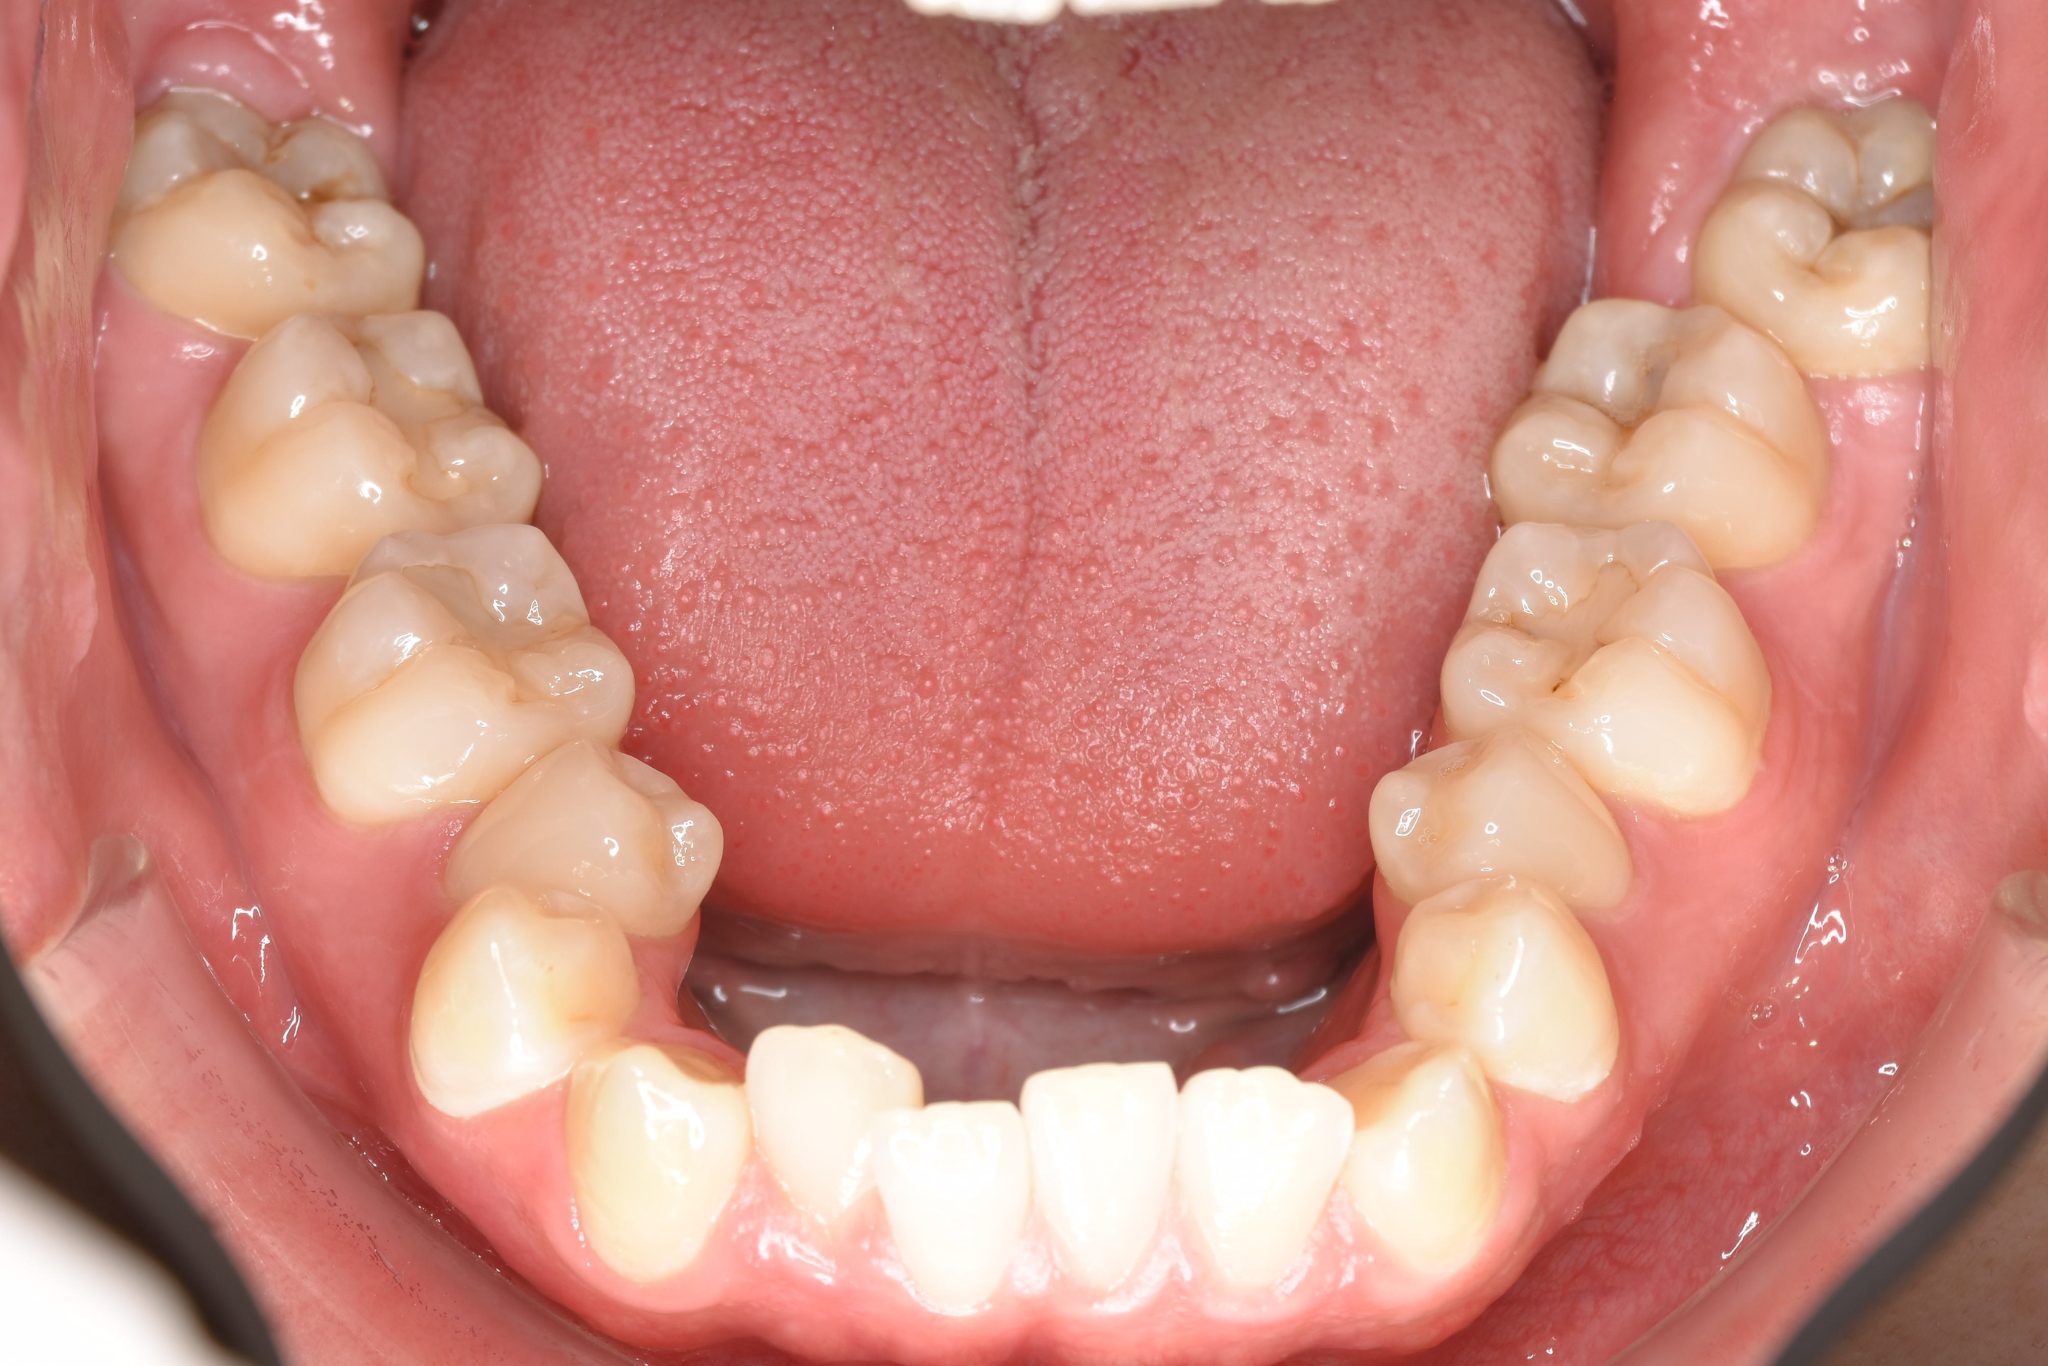

アフター

ワイヤー矯正治療|症例_495

主訴 受け口|かみ合わせ|面長

施術内容 MSEと下顎リンガルアーチを用いて上下顎骨を拡大した。

その後マルチブラケット装置とミニインプラントを用いて

非抜歯で歯牙を配列し、良好な咬合を獲得した。

下口唇の突出感と鼻閉症状は改善した。

治癒期間 2年1か月間